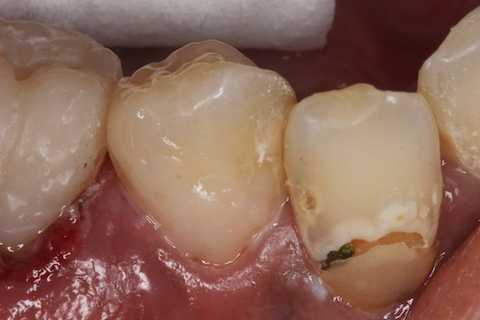

残根上のCR8 2025.10.28